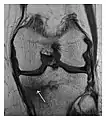

Figure 9: Proximal metaphyseal fatigue fracture of the tibia in a 27-year-old recent male military recruit. (a) Anteroposterior radiograph is within normal limits. (b) Coronal T1-weighted MR image shows a marked linear hypoattenuation along the medial tibial metaphysis (arrow) surrounded by diffuse hypointensity in keeping with posttraumatic edema.[1]

a

b